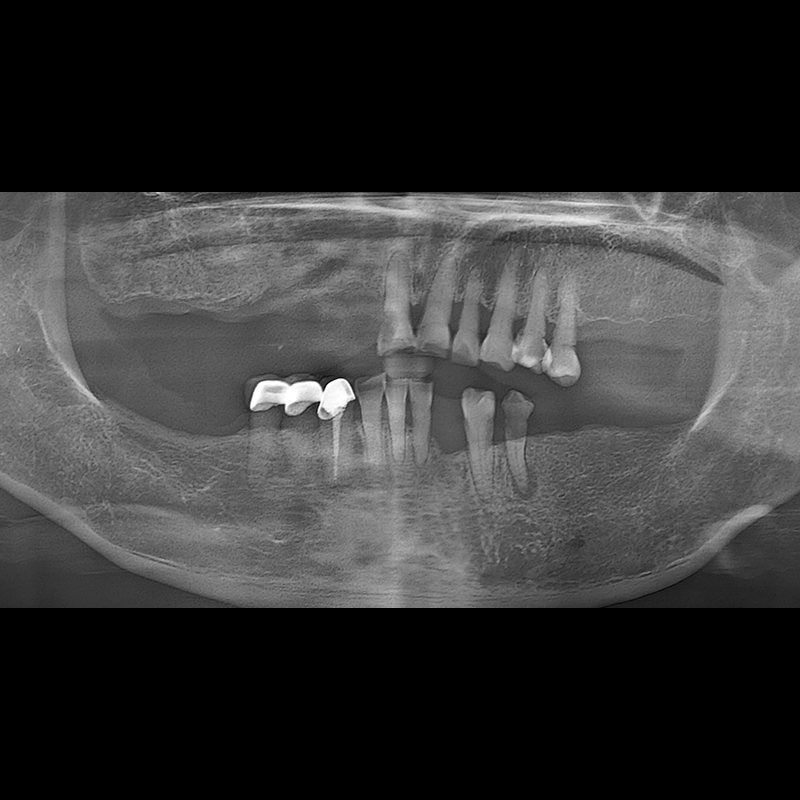

BEFORE AFTER

Implant before and after 2025.05.30

Implants were placed in the missing tooth and in the tooth position where it was difficult to save.